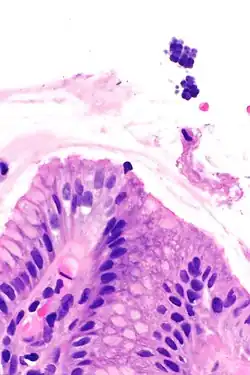

Gastric mucosa and Sarcina on upper right. H&E stain.

Sarcina is a genus of gram-positive cocci bacteria in the family Clostridiaceae.[2][3][4] A synthesizer of microbial cellulose,[5] various members of the genus are human flora and may be found in the skin [6] and large intestine.[7] The genus takes its name from the Latin word "sarcina," meaning pack or bundle, after the cuboidal (2x2x2) cellular associations they form during division along three planes.[8]

The genus's type species is Sarcina ventriculi, a variety found on the surface of cereal seeds, in soil, mud, and in the stomachs of humans, rabbits, and guinea pigs.[9]